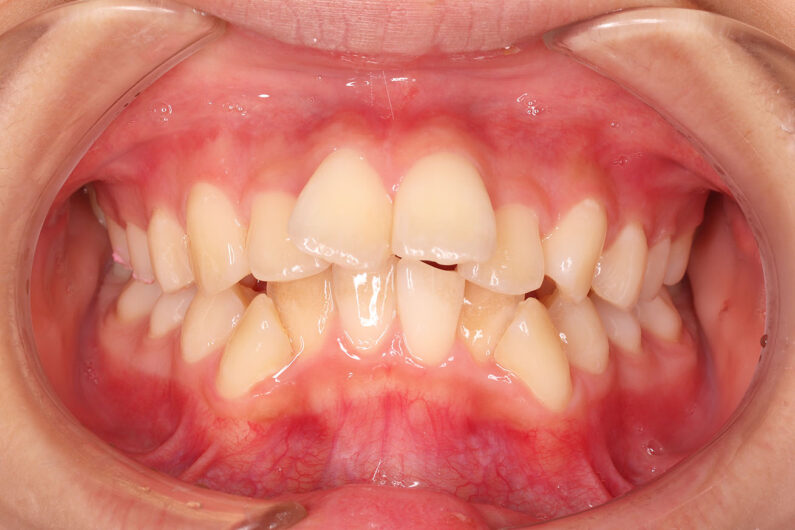

他院から紹介の患者さんです。 前歯、下の歯のガタツキをきれいにしたいということで治療を決断されました。

上顎前歯6mm、下顎前歯2.5mmの前突の状態で、口唇も前突しています。 小臼歯抜歯したスペースを使い、叢生(がたつき)と前突した前歯の後退を目標にしました。 この方も希望により、アンカースクリューは使用せず、通常の顎間ゴムで対処してもらいました。